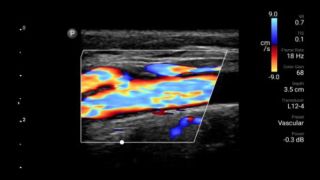

Reduce complications in needle guided procedures

Lumify handheld ultrasound for anesthesiology helps you clearly visualize border definition with your needle placement, surrounding nerves, vessels and fascial planes.